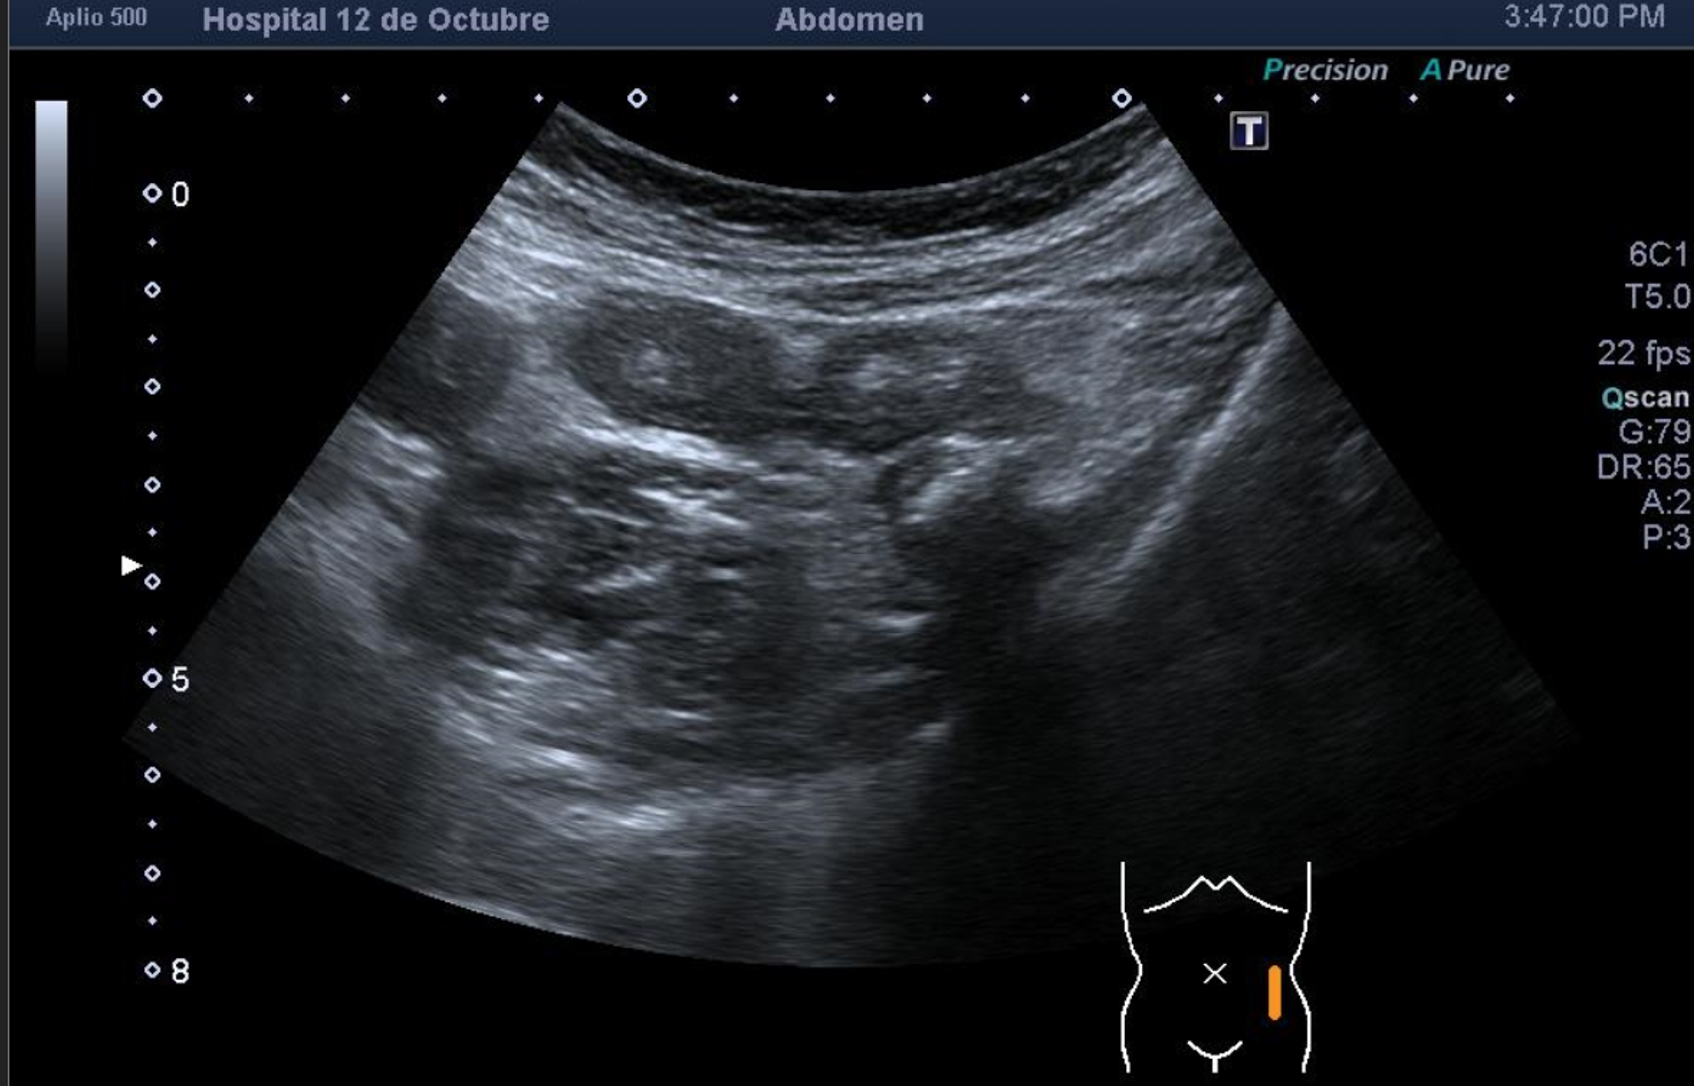

Hallazgos ecográficos

Se explora FII-hipogastrio y en el punto de más dolor se observa engrosamiento de asas de intestino grueso sin peristaltismo y con signos de edema de la grasa adyacente. No líquido libre.

Ante la sospecha de diverticulitis aguda se deriva a urgencias hospitalarias.

En el hospital se realiza una nueva ecografía en el servicio de radiología confirmando el diagnóstico de sospecha: diverticulitis aguda en sigma distal sin datos de complicación. Hinchey 1A.